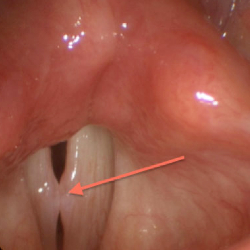

Vocal nodule

Vocal nodules, also known as singer’s nodules or vocal cord nodules, are benign growths or calluses that form on the vocal cords. They are typically caused by excessive strain or overuse of the vocal cords, and are most commonly found in individuals who use their voice professionally, such as singers, actors, and public speakers. Symptoms of vocal nodules may include hoarseness, difficulty speaking or singing, a scratchy or rough voice, and vocal fatigue. Treatment options may include vocal rest, speech therapy, and in some cases, surgery.

Voice assessment

Voice assessment in ENT involves the evaluation of a patient’s vocal function to diagnose and treat various voice disorders. The assessment typically begins with a comprehensive medical history and physical examination of the patient’s larynx and vocal cords. Additional tests may include acoustic analysis of the voice, which measures factors such as pitch, loudness, and vocal quality, as well as perceptual analysis, which evaluates the listener’s subjective impression of the voice. Other specialized tests such as laryngoscopy or stroboscopy may also be used to visualize the vocal cords during speech or singing. Based on the results of the assessment, the ENT specialist can develop an individualized treatment plan, which may include voice therapy, medication, or surgical intervention.